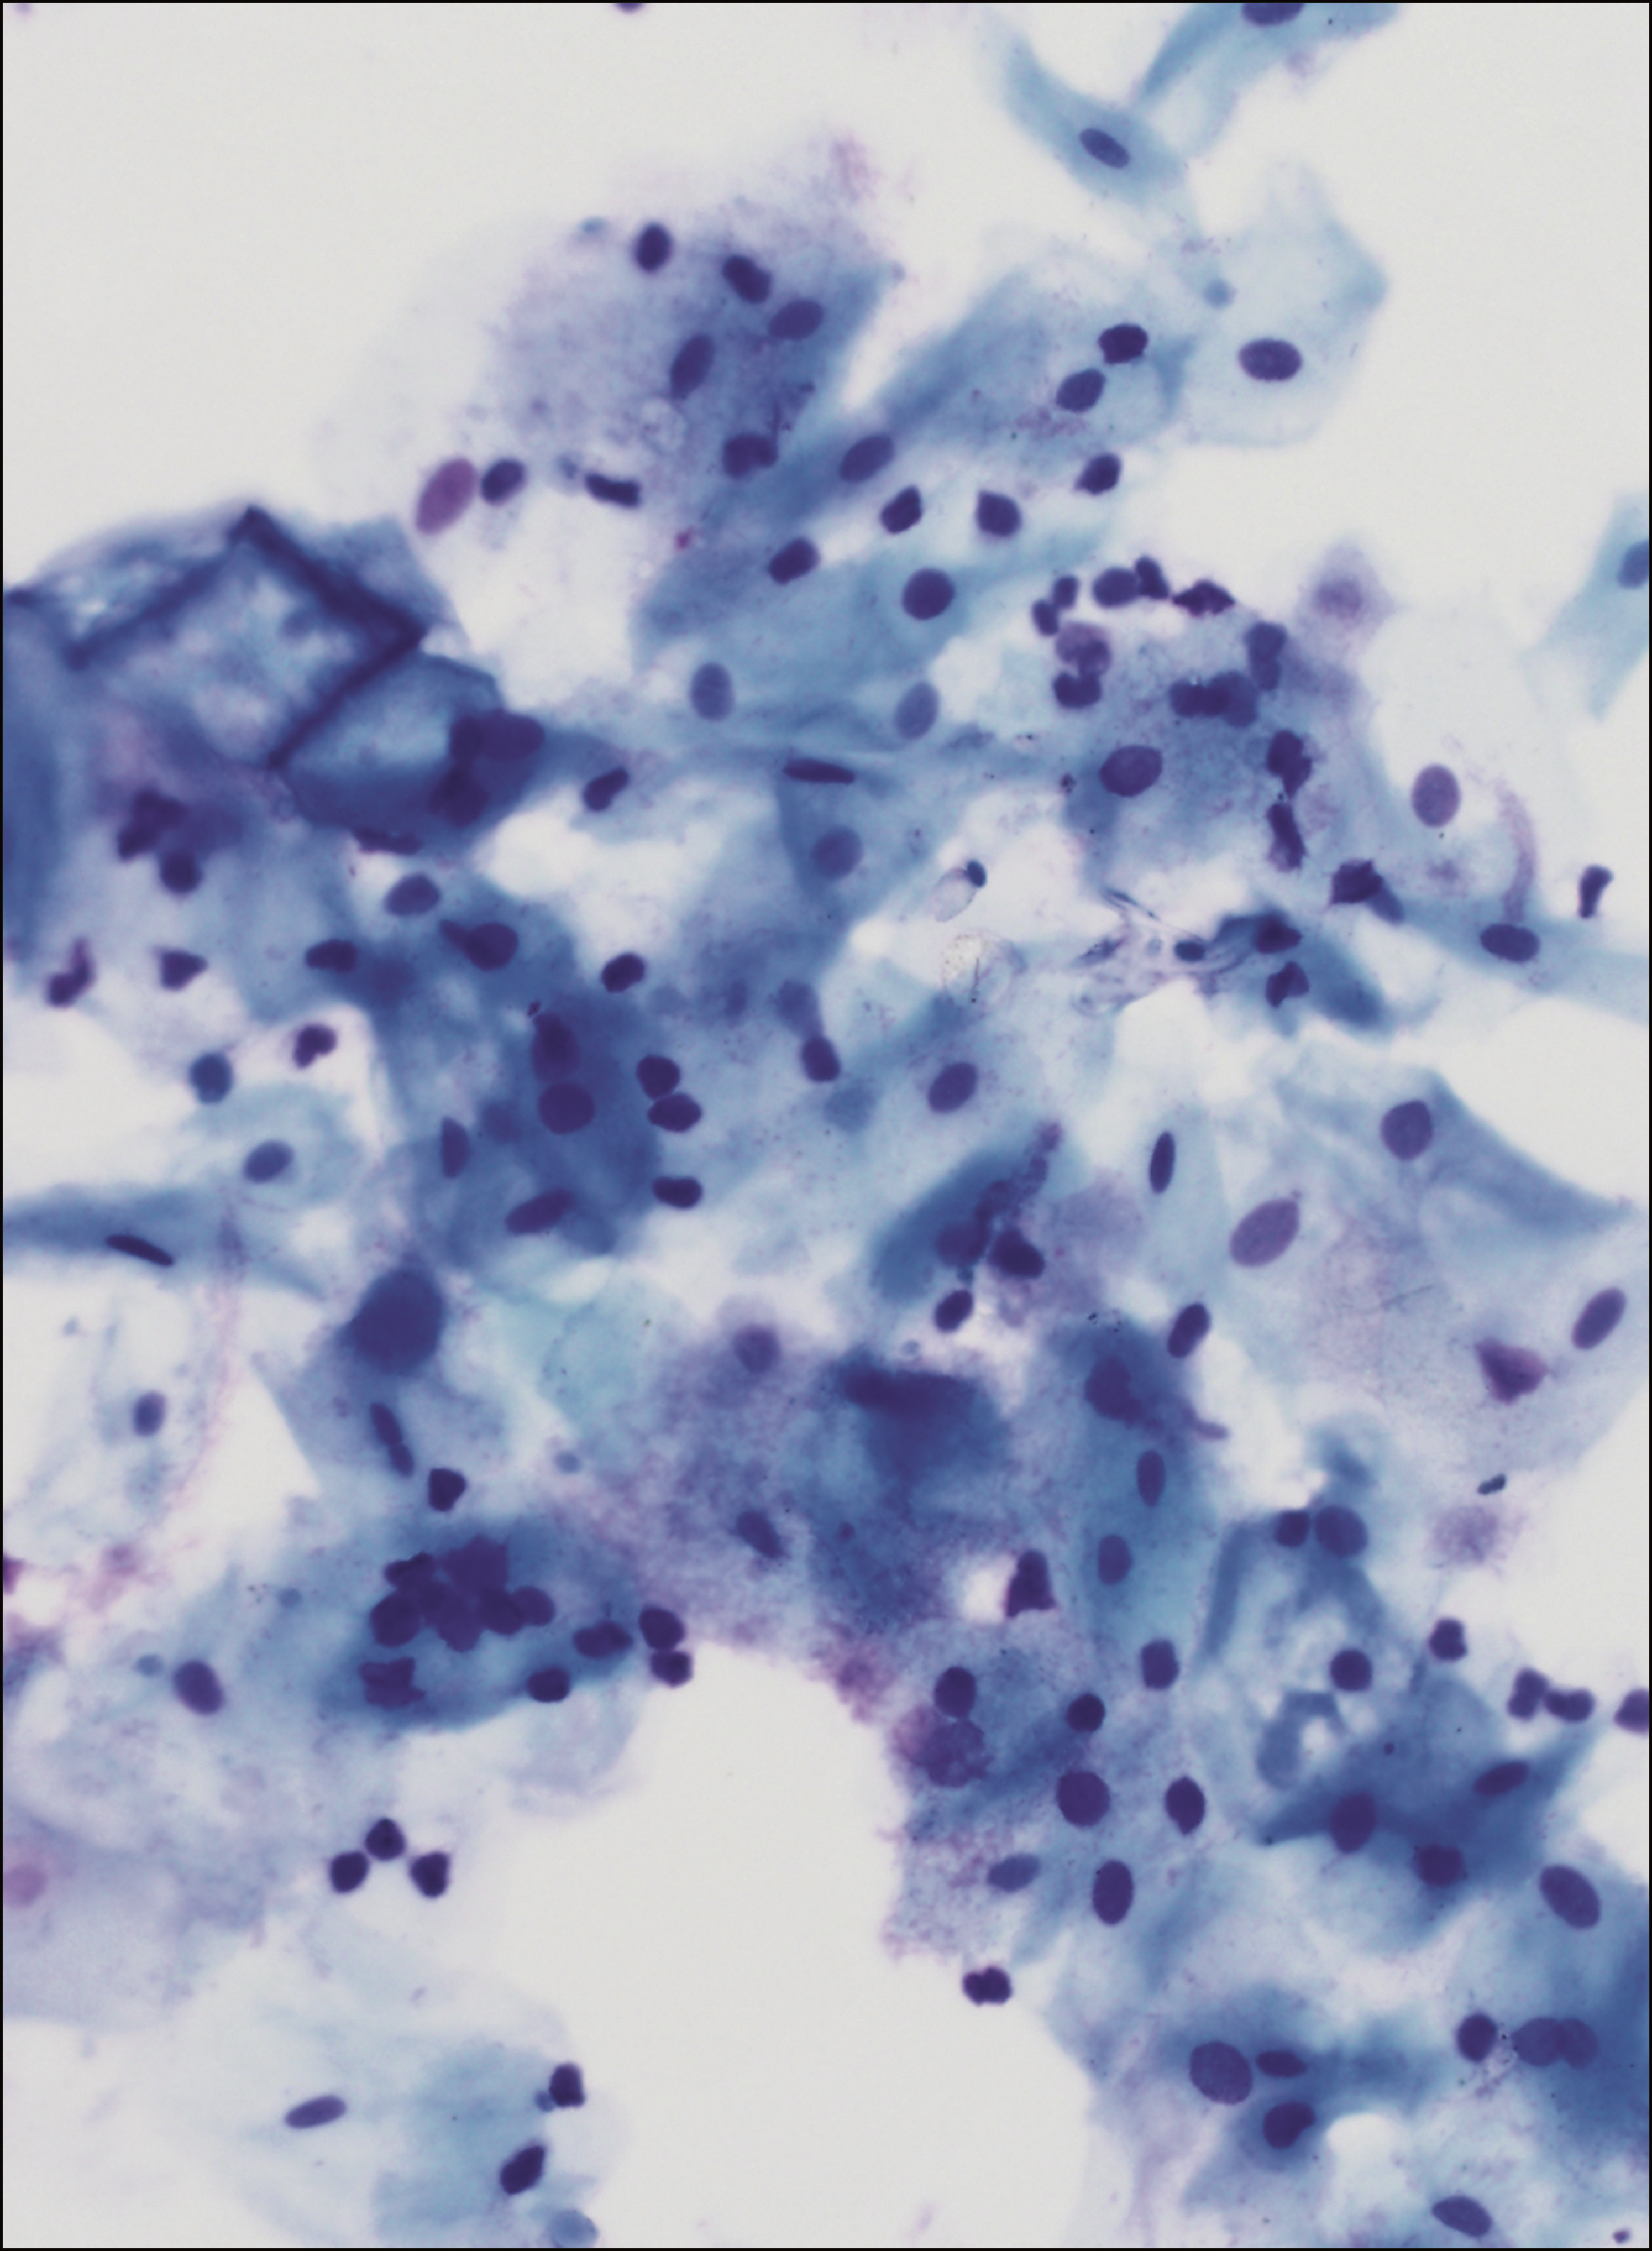

COVER FIGURE

Buccal epithelial cells harboring a sporadic myeloproliferative neoplasm–associated CALR mutation. See the article by Gilles et al. - PDF Icon Front MatterFront Matter